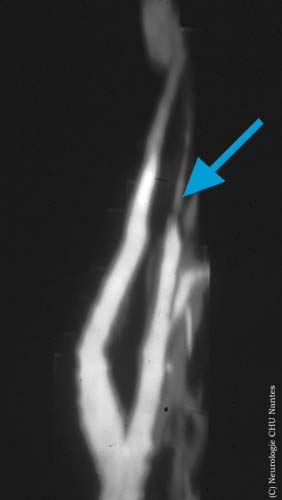

Aspect de l'angioRM lors d'une dissection carotidienne

Commentaires: Disparition du signal de flux sur cette artère. L'arrêt du flux donne une image effilée en queue de radis